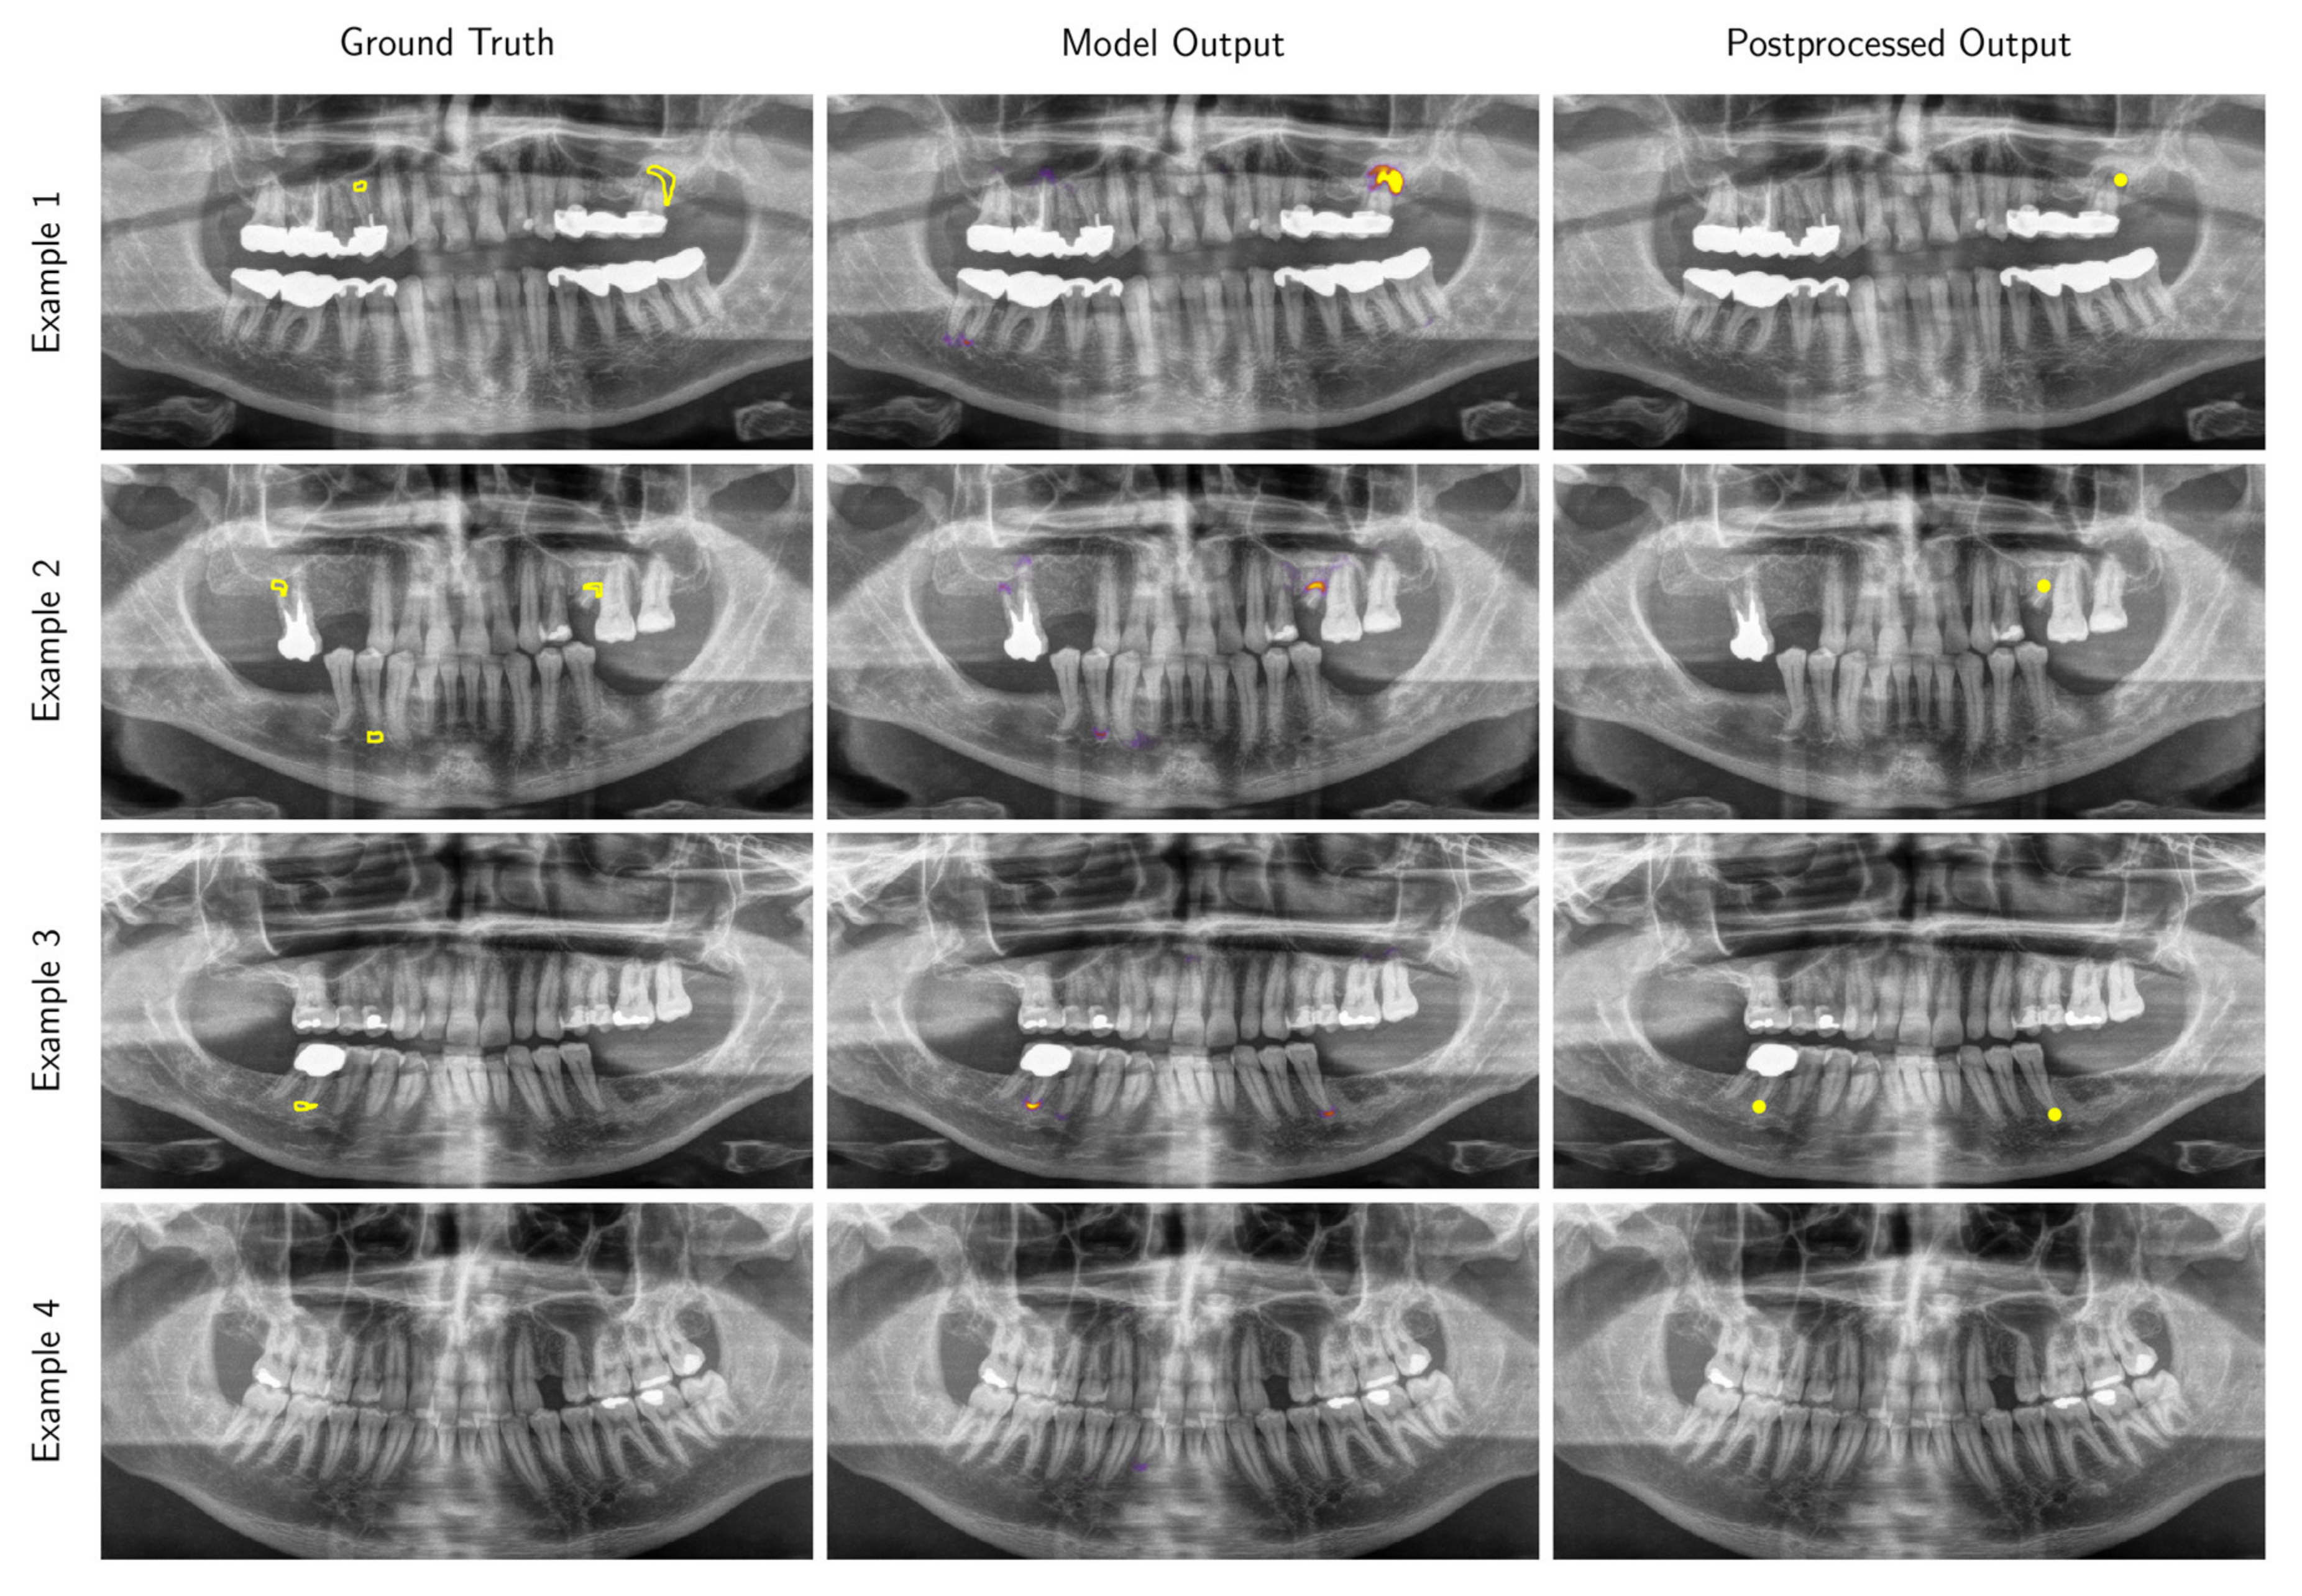

3.2. Performance of the Deep Learning Algorithm